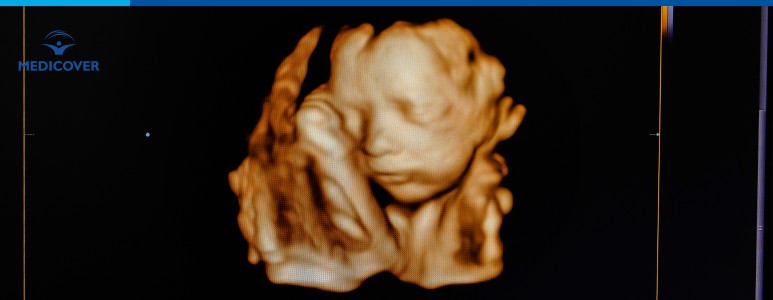

Denumirea de dublu test vine de la faptul ca testul presupune realizarea a doua investigatii specifice in primul trimestru de sarcina, la un interval mai mic de 24 de ore. Prima investigatie este o examinare ecografica, iar cea de-a doua este un examen de sange al mamei, care analizeaza doi markeri biochimici esentiali: PAPP-A și HCG liber.